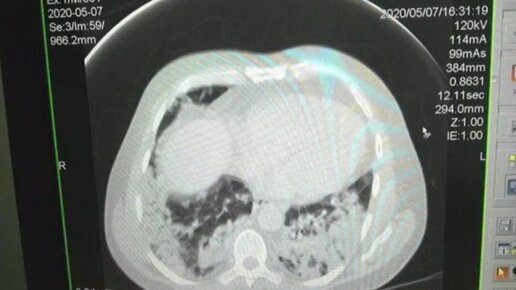

Врачи показали, как выглядят легкие заболевшего covid 19

В Ростовской области врачи показали, как выглядят легкие заболевшего covid 19 . По их словам, поражение дыхательной системы выдает наличие на снимке «эффекта матового стекла». Это свидетельствует о том, что человеку трудно дышать потому, что в его легкие поступила кровь, пишет 59.ru. По словам врачей, светлые участки, именуемые матовым эффектом, говорят о том, что начался необратимый процесс. «Эффект матового стекла» на легких проявляется даже у тех, кто перенес заболевания без проявления симптомов, врачи Ростовской области...